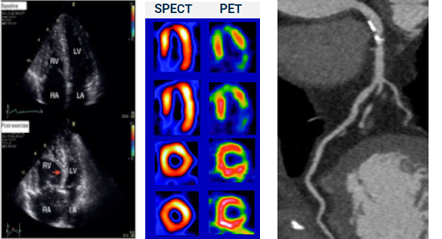

Traditional NITs vs. Heartflow | |||

Stress Echocardiogram | SPECT and PET | CCTA | Heartflow FFRCT Analysis |